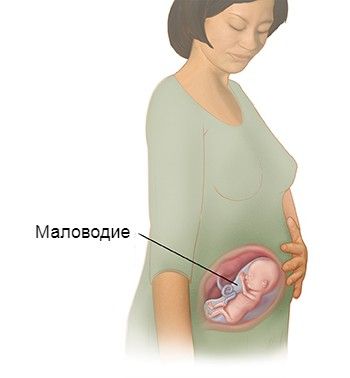

Медицинские аспекты мекония в околоплодных водах